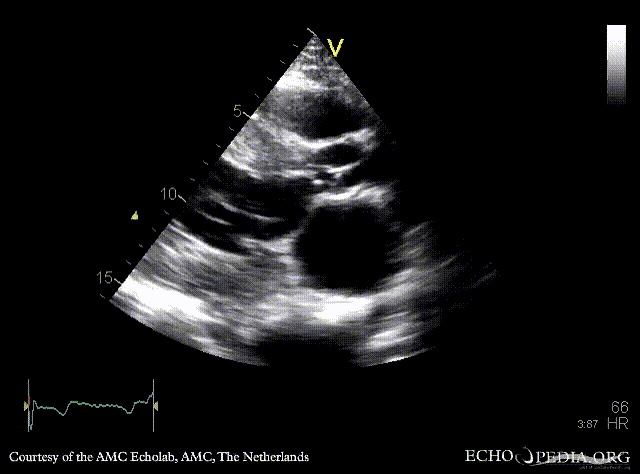

A3CH A3CH with Color Doppler